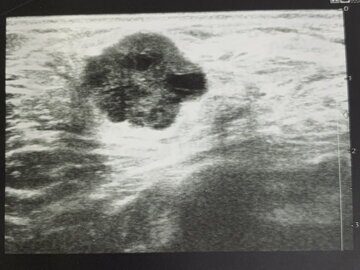

УЗИ рак груди

Фото УЗИ опухоли одной и той же пациентки с интервалом 4 месяца. Первый раз врачом УЗИ был проигнорирован неровный контур опухоли и её большой вертикальный размер. Через 4 месяца был замечен рост образования, но снова проигнорирован вертикальный размер и неровный контур. На всех этих снимках УЗИ – рак молочной железы.